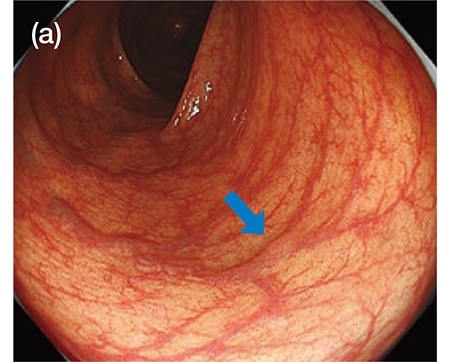

During screening tests, the key point of lesion detection is certain capturing of changes in color tones and unevenness of the mucosal surface under WLI or NBI in middle to long distance view during scope withdrawal. In corporation of a highly sensitive CMOS image sensor chip into the XZ1200 achieved noise reduction and high resolution image. I find that these improvements in image quality enables clear imaging in middle to long distance view, as compared to conventional models. Therefore, it appears that slight changes in unevenness and color tones (such as pale redness) of the lesion are captured more clearly under WLI (Fig. 1a). The improvements in image quality also could be realized in observations under NBI. In my first experience utilizing NBI with the XZ1200, I was deeply impressed by the differences in image clarity from previous models. I find that observations under NBI by using the XZ1200 will increase the lesion detection rate because of improved visibility of brownish areas even for flat or depressed lesions with only little unevenness. Because the lesion detection is the most important outcome of screening, I think that the observation performance advanced by these improvements is one of the greatest benefits of the XZ1200.

[Fig. 1]Images of the same lesion in middle distance view obtained by the XZ1200 under WLI (a) and TXI (Mode 1) (b)

(a) WLI